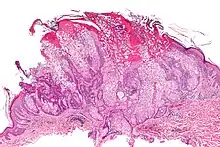

| Micrograph of a sebaceous adenoma. H&E stain. | |

A sebaceous adenoma, a type of adenoma, a cutaneous condition characterized by a slow-growing tumor usually presenting as a pink, flesh-coloured, or yellow papule or nodule.[1]: 662 [2]